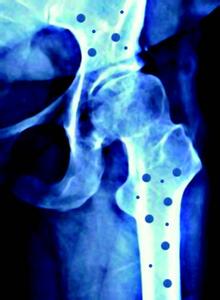

骨折后大量补钙不可取

骨折

不少人认为骨头断了,当然要补,而骨骼主要由钙组成,骨折后补钙是理所当然的事。于是,各种各样的补钙方法齐齐上场。骨头汤是大家最常用的方法,此外,喝牛奶、吃钙片也不能少。国康实业最新91视频网站厂家提醒大家骨折后不可大量补钙,也不可乱补,否则会适得其反。

骨折的发生多由创伤或其它病理因素所致,并非由机体缺钙而引起。恰恰相反,在骨折发生后,骨折的断端还会释放出大量的钙质。同时,由于骨折部位又很容易导致全身或局部骨骼废用性脱钙。这两种脱失的钙盐可形成游离钙被吸收入血,使血钙的含量增高,血钙是由肾脏进入代谢的,此时再摄入大量的钙剂,势必会增加肾脏的代谢负担,严重者还会引起其他骨科疾病。

再有,骨的早期再生主要依靠骨膜、骨髓的作用,而骨髓只有在增加骨胶原的条件下,才能较好的发挥作用。如果骨折后短期内摄入大量的钙,会使骨质内无机质成分增多,有机质与无机质比例失调,反而会阻碍骨折的早期愈合。

大量的服用钙剂还能引起胃酸减少、食欲不振、消化不良及呕吐、 腹泻 等胃肠道症状,这些不良反应很容易导致患者的营养障碍,反会影响骨折的愈合。机体在新陈代谢过程中,需要的钙盐是有一定限度的,一般正常 饮食 所摄入的钙盐就能满足生理上的需要。